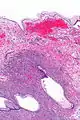

| Micrograph showing a mucinous cystadenoma of the ovary. H&E stain. | |

Mucinous cystadenoma is a benign cystic tumor lined by a mucinous epithelium.